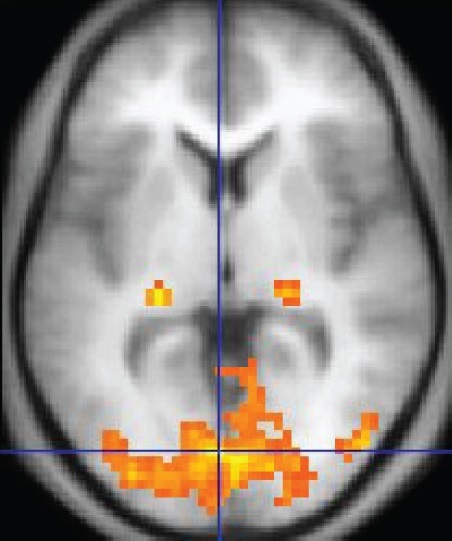

신경과학자들은 뇌 영상 기술을 주요 연구 방법으로 사용한다. 기능적 자기공명영상(fMRI)은 혈류와 관련된 뇌의 자기장 변화를 측정한다. 혈류가 증가한 영역은 해당 뇌 영역이 특히 활동적임을 나타낸다. 양전자 방출 단층 촬영(PET)은 방사성 물질을 사용하여 뇌의 다양한 대사 변화를 감지한다. 뇌파(EEG)는 일반적으로 두피에 전극을 놓고 전극 사이의 전압 차이를 측정하여 뇌의 전기 활동을 측정한다. 이러한 기술은 종종 특정 상황, 예를 들어 특정 인지 과제에 참여하는 동안 뇌의 변화를 측정하는 데 사용된다. 특정 영역에 뇌 손상이 있는 환자와 실험 동물로부터 중요한 통찰력을 얻어 손상된 영역의 기능과 그 부재가 나머지 뇌에 어떤 영향을 미치는지 평가한다.[154]